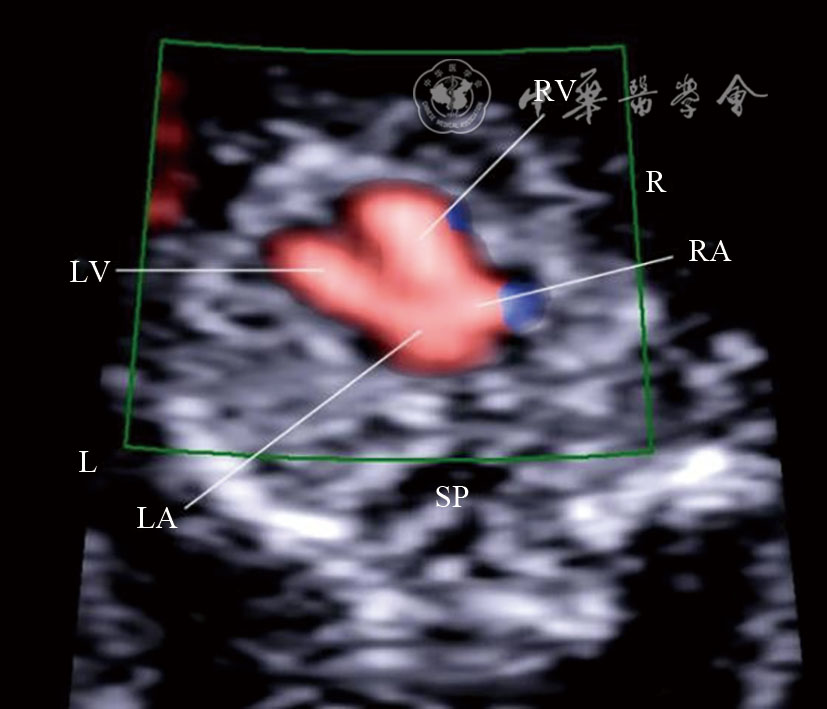

图9 妊娠12+5周胎儿心尖四腔心切面彩色多普勒血流成像 注:LV为左心室;RV为右心室;LA为左心房;RA为右心房;SP为脊柱;R为右侧;L为左侧